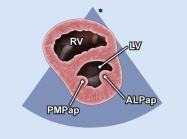

| 2.12. Mặt cắt trục ngắn cạnh ức (ngang mức các cơ nhú) |

||||||||

|

|

Cửa sổ siêu âm cạnh ức Mặt cắt trục ngắn cạnh ức Từ vị trí van hai lá gập đầu dò xuống dưới |

Thất phải (RV)

Vách liên thất (IVS) Cơ nhú sau giữa (PMPap) Cơ nhú trước bên (ALPap) Thất trái (LV) |

|||||